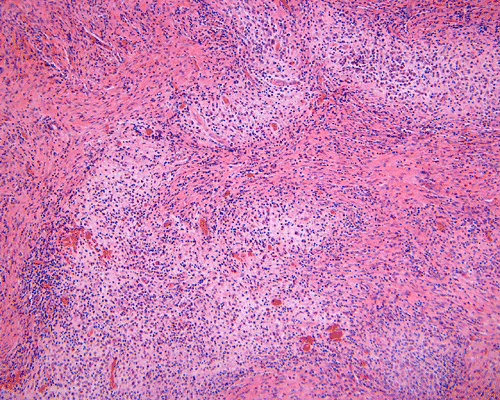

Morphologic features are often sufficient to make an accurate diagnosis. Typical lesions are composed of medium sized to large Langerhans’ cells mixed with non-neopalstic inflammatory cells. The amount of eosinophils can vary from none 3 or scant to substantial. The Langerhans’ cells have only slight degree of atypia. Many of the nuclei have a characteristic deep groove parallel to the long axis, the so-called “coffee bean” nuclei. The amount of cytoplasm is usually moderate. Histiocytes (macrophages) are usually present and can be multinucleated. When histiocytes are present in large amount, they may make the diagnosis difficult. Similar to their non-neoplastic counterparts, tumor cells in Langerhans’ cell histiocytosis are positive for CD1a and S100 by immunohistochemistry. Histiocytes, on the other hands, are negative for S100 and CD1a 4, 5, 6 CD68 is helpful but not entirely specific in separating histiocytes from tumor cells in Langerhans’ cell histiocytosis. The proliferating fraction of can be recognized by immunohistochemistry for Ki67 (MIB-1) 6.

DIAGNOSIS: Langerhans' cell histiocytosis. |